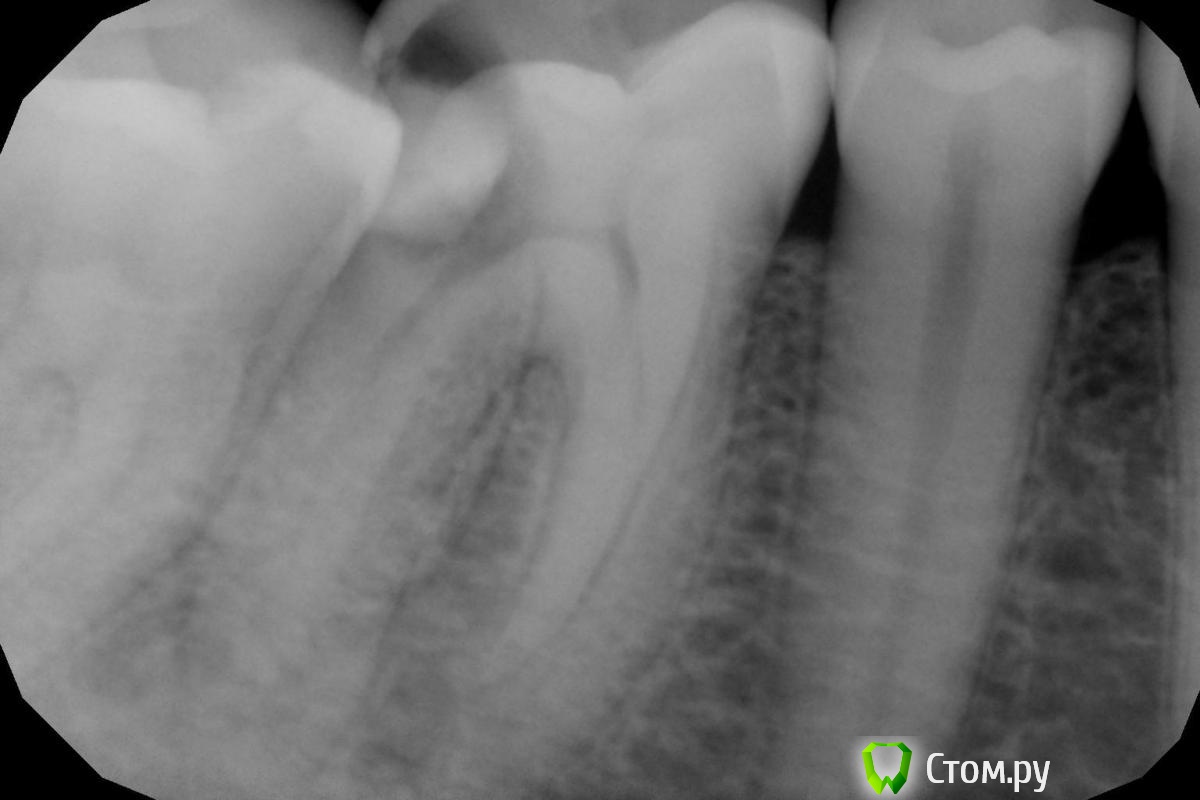

Паращук Роман Опубликовано 21 сентября, 2014 Поделиться Опубликовано 21 сентября, 2014 Пообсуждаем... http://s017.radikal.ru/i429/1409/43/d9acfcd05579.jpg Вы все еще надеетесь на ГХ и инертный силлер?ПиСи Не троллинга ради,а цимуса за. Ссылка на комментарий

_omega- Опубликовано 21 сентября, 2014 Поделиться Опубликовано 21 сентября, 2014 (изменено) Пообсуждаем... http://s017.radikal.ru/i429/1409/43/d9acfcd05579.jpg Вы все еще надеетесь на ГХ и инертный силлер?ПиСи Не троллинга ради,а цимуса за.Не хочется работать после такого вот..... Изменено 21 сентября, 2014 пользователем _omega- Ссылка на комментарий

Shaid Опубликовано 22 сентября, 2014 Поделиться Опубликовано 22 сентября, 2014 Думаете, ультразвук поможет в такой системе корневых каналов? Ссылка на комментарий

Girl Опубликовано 25 сентября, 2014 Поделиться Опубликовано 25 сентября, 2014 Сегодня шестерку лечила. Не очень поняла снимки По поводу дистального канала - если верить апексу, то я от апекса 0,5 мм. Пересняла отдельно дистальный канал с инструментом на размер меньше, тоже руководствуясь апекс-локатором, и все равно на снимке не дохожу. Почему так? Канал латерально открывается? И вообще, есть ощущения третьего корня 1 Ссылка на комментарий

Shaid Опубликовано 26 сентября, 2014 Поделиться Опубликовано 26 сентября, 2014 Т.е. аплок не показывал значение "за апексом"? Файл дальше тоже не идет? Ссылка на комментарий

Girl Опубликовано 26 сентября, 2014 Поделиться Опубликовано 26 сентября, 2014 (изменено) Аплок показывао, что я у самого апекса.Канал достаочно широкий, и за апекс тоже можно выйти. Я обычно 0, 5 мм не довожу, делаю снимок и пломбирую? А на этом снимке не вижу, что я до конца прошла...Вы думаете, я промахнулась и перфанула корень? Зуб 46, забыла сказать. Изменено 26 сентября, 2014 пользователем Girl Ссылка на комментарий

kitikf Опубликовано 26 сентября, 2014 Поделиться Опубликовано 26 сентября, 2014 Может быть 2 дистальных , причём начинается одним широким , а потом идёт раздвоение . В одно вы как раз попадаете. Ссылка на комментарий

Girl Опубликовано 27 сентября, 2014 Поделиться Опубликовано 27 сентября, 2014 Может быть 2 дистальных , причём начинается одним широким , а потом идёт раздвоение . В одно вы как раз попадаете.А если я так и не попаду во второй, каков прогноз? Через несколько лет вторичное эндо? ( Ссылка на комментарий

kitikf Опубликовано 27 сентября, 2014 Поделиться Опубликовано 27 сентября, 2014 (изменено) Если бы я не смогла его найти , то объяснила бы пациенту что сделала всё возможное , что дополнительный канал склерозировался и запломбировала бы проходимую часть или сделала бы депофорез с гидроокисьюмеди . А дальше наблюдать. Изменено 27 сентября, 2014 пользователем kitikf Ссылка на комментарий